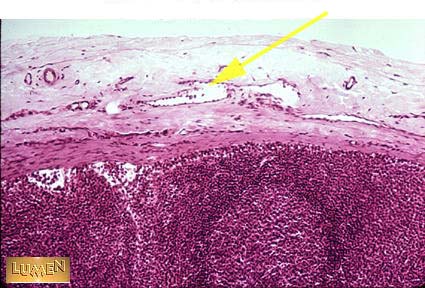

What vessel is this?

Answer

Afferent Lymph vessel